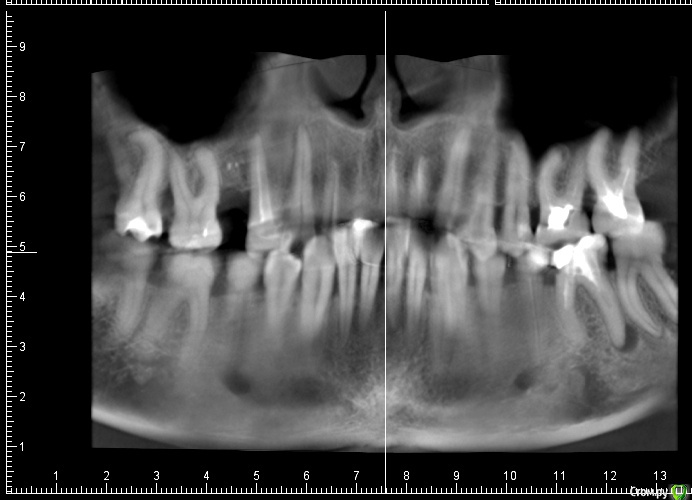

ceti Опубликовано 18 декабря, 2015 Поделиться Опубликовано 18 декабря, 2015 Здравствуйте! Зуб 37 с недавнего времени стал безпокоить, ощущается дискомфорт, тянущие ощущения в районе скулы. На осмотре доктор обнаружил паталогический карман через который отделяется гной или серозная жидкость. Сделали КТ: Полностью, вся томограмма: https://drive.google.com/open?id=0BwAD98i97KuPbUpFdGcxeXRNMjg Предыдущий КТ (февраль этого года): https://drive.google.com/open?id=0BwAD98i97KuPflhOam1lTzJsTkhBNFNVdUFmb3lHWWJ3Rll2Z1BTVDUteURyNTNUdElSems Насколько я понимаю, в феврале проблемы не было вообще, либо она была незначительна. Зуб несколько раз травмировался -- во время еды попадал твердый предмет, достаточно неприятное чувство. Вероятно, вследствие этого на жевательной поверхности появился скол пломбы, место скола чувствительно к прикосновению зондом. Также (возможно это важно) намного ранее было сильное воспаление связанное с соседним 8-ым зубом. Тоже был обширный карман, эту 8-ку удалили лет пятнадцать назад. Еще, полгода назад было проведено перелечивание каналов соседнего 36 зуба. Посоветуйте пожалуйста стоит ли пытаться лечить этот зуб или лучше его удалить. На консультации мне предложили такую последовательность действий: 1) Эндодонтия под микроскопом2) Кюретаж (вероятно открытый)3) Остеопластика4) Плазмалифтинг Есть ли смысл пробовать и насколько велики шансы на успех? Если зуб нужно удалять, то насколько срочно. Еще, соседний зуб 36 имеет воспаление у верхушки корня соседнего с 37, есть ли риск его задеть при удалении 37-го зуба? Заранее благодарю за ответ. Ссылка на комментарий

ceti Опубликовано 21 декабря, 2015 Автор Поделиться Опубликовано 21 декабря, 2015 Здравствуйте! По результатам очного осмотра доктор исключил трещину и предположил парадонтальную проблему. Есть какое-то объяснение, что могло послужить причиной и почему процесс так быстро прогрессировал? Ниже фрагмент КТ, который был сделан в феврале этого года и свежий снимок: Заранее благодарю. Ссылка на комментарий